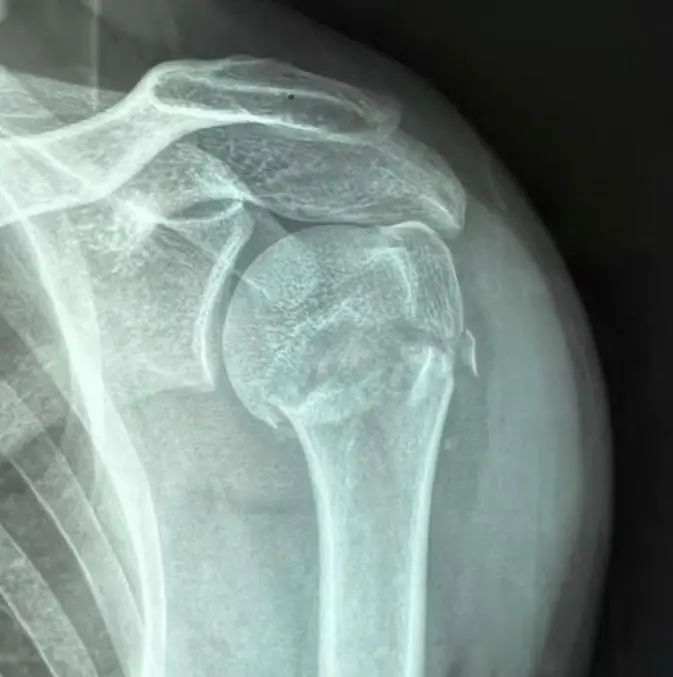

肱骨(gu)(gu)近端(duan)骨(gu)(gu)折是肩部(bu)常(chang)見的骨(gu)(gu)折類(lei)型,多見于老年(nian)人和骨(gu)(gu)質疏松(song)患(huan)者。這種骨(gu)(gu)折不僅影(ying)響肩關節的功能,還可能導致長期的疼(teng)痛和活動(dong)受限。

AO分型(xing)

AO分(fen)型(xing)(xing)基于肱骨(gu)近端(duan)骨(gu)折的解剖(pou)位(wei)置和復(fu)雜性,分(fen)為三大類(lei)(A、B、C型(xing)(xing)),每型(xing)(xing)再細(xi)分(fen)為亞型(xing)(xing):

A型 關節外單處骨折

A1:大結節骨(gu)折

A2:外科(ke)頸骨折,嵌插(cha)型

A3:外科頸骨折,非嵌(qian)插(cha)型

B型 關節外兩處骨折

B1:外(wai)科頸骨折(zhe)伴大(da)結節骨折(zhe)

B2:外科(ke)頸骨折伴(ban)小結節骨折

B3:外(wai)科頸(jing)骨折伴肩關節脫位

C型 關節內(nei)骨(gu)折

C1:關(guan)節內(nei)骨折,輕度移位(wei)

C2:關節內骨折,明顯移位

C3:關(guan)節內骨折(zhe),肱骨頭(tou)劈裂或脫位